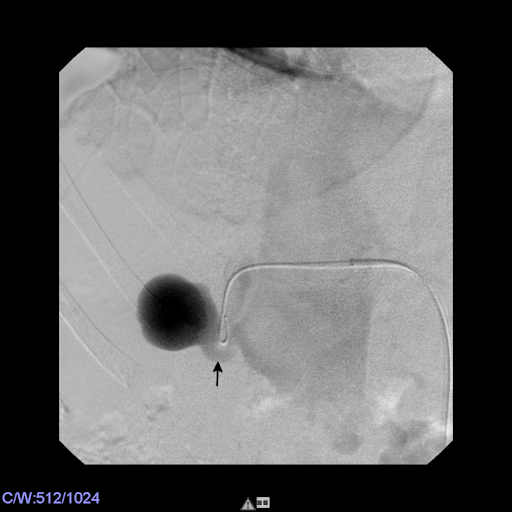

This maneuver was followed by careful placement of a 5 F Berenstein catheter (Cordis) within the AVF via the transvenous access. After angiographic confirmation of correct position, an Amplatzer vascular plug IV, 7 mm (St. Jude Medical, St. Paul, MN, USA) was deployed within the venous segment of the AVF and completely occluded the fistula (Figure 5 [Fig. 5]).

Figure 5: The venous segment of the AVF was occluded by deployment of an AVP IV, 7 mm. The radiopaque markings of the AVP are clearly visible (arrows). Note that the fistula is completely sealed by the occluder, the inflow into the aneurysm of the renal artery (upstream of the AVP) is overprojected with the AVP.